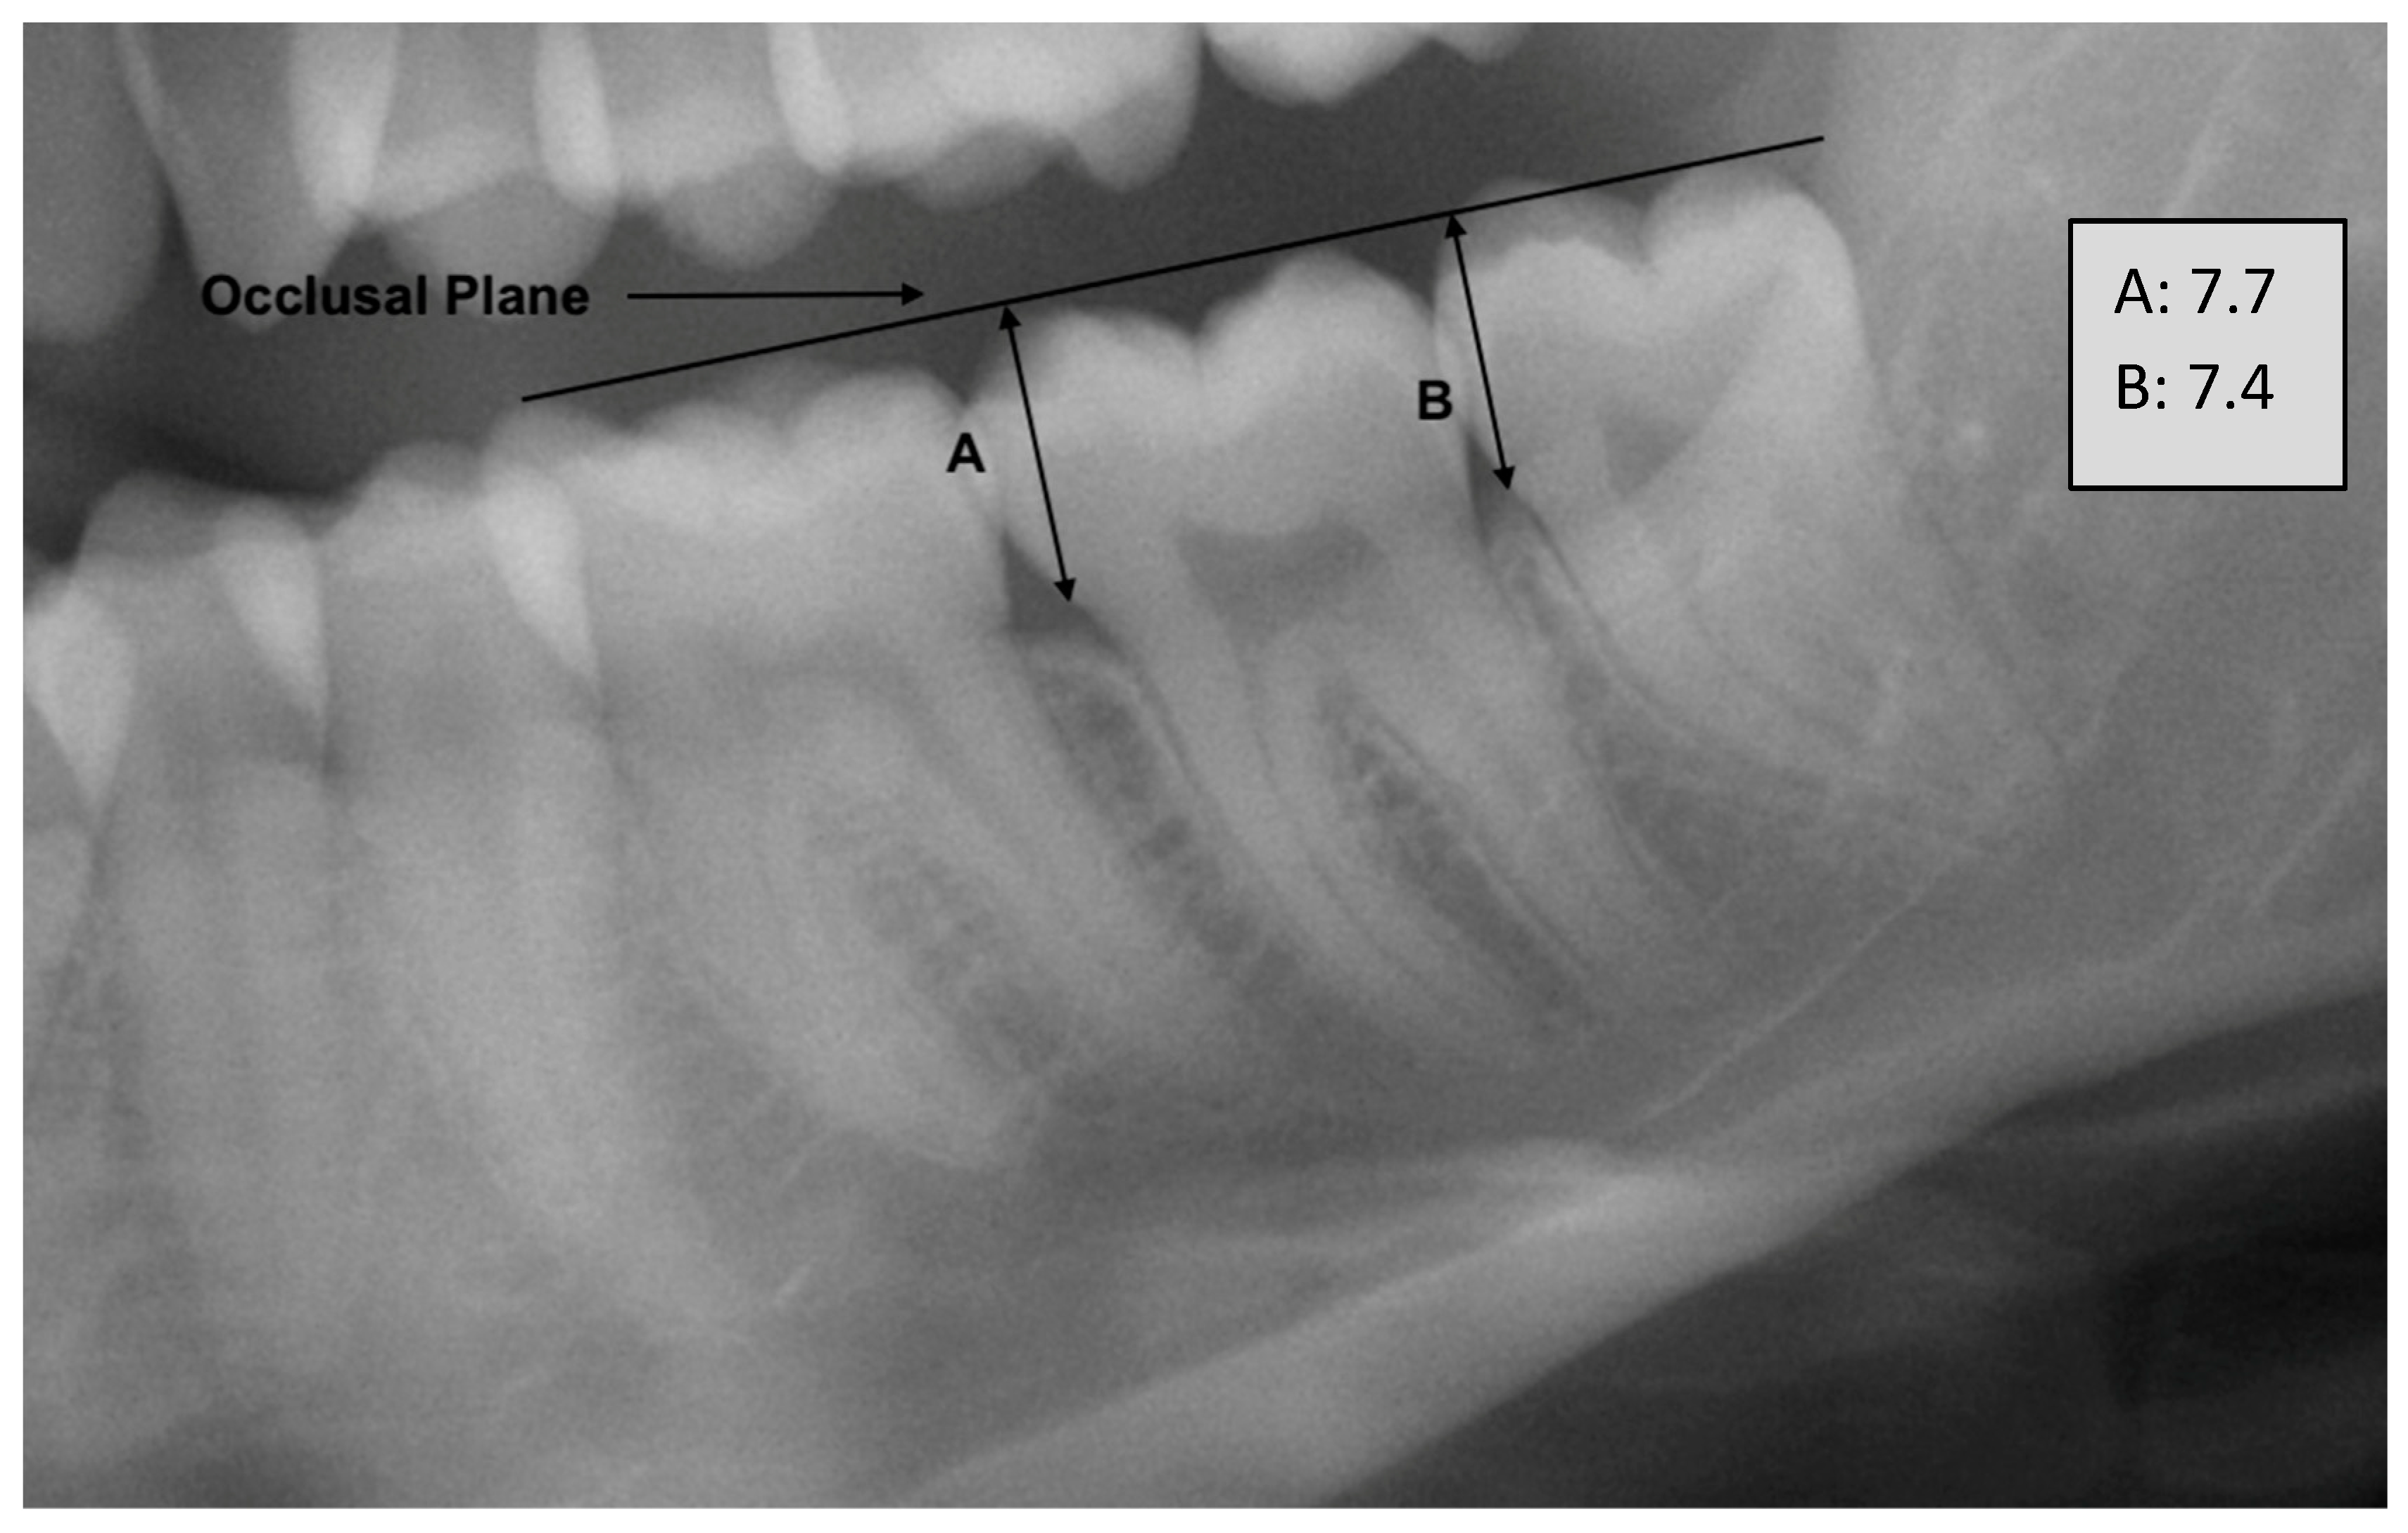

- Wedl, J.S.; Friedrich, R.E. Die Abstandsmessung der Weisheitszähne zur Okklusionsebene als forensisch-odontologisches Hilfsmittel zur Bestimmung des chronologischen Alters. Arch. Kriminol. 2005, 215, 77–84. [Google Scholar]